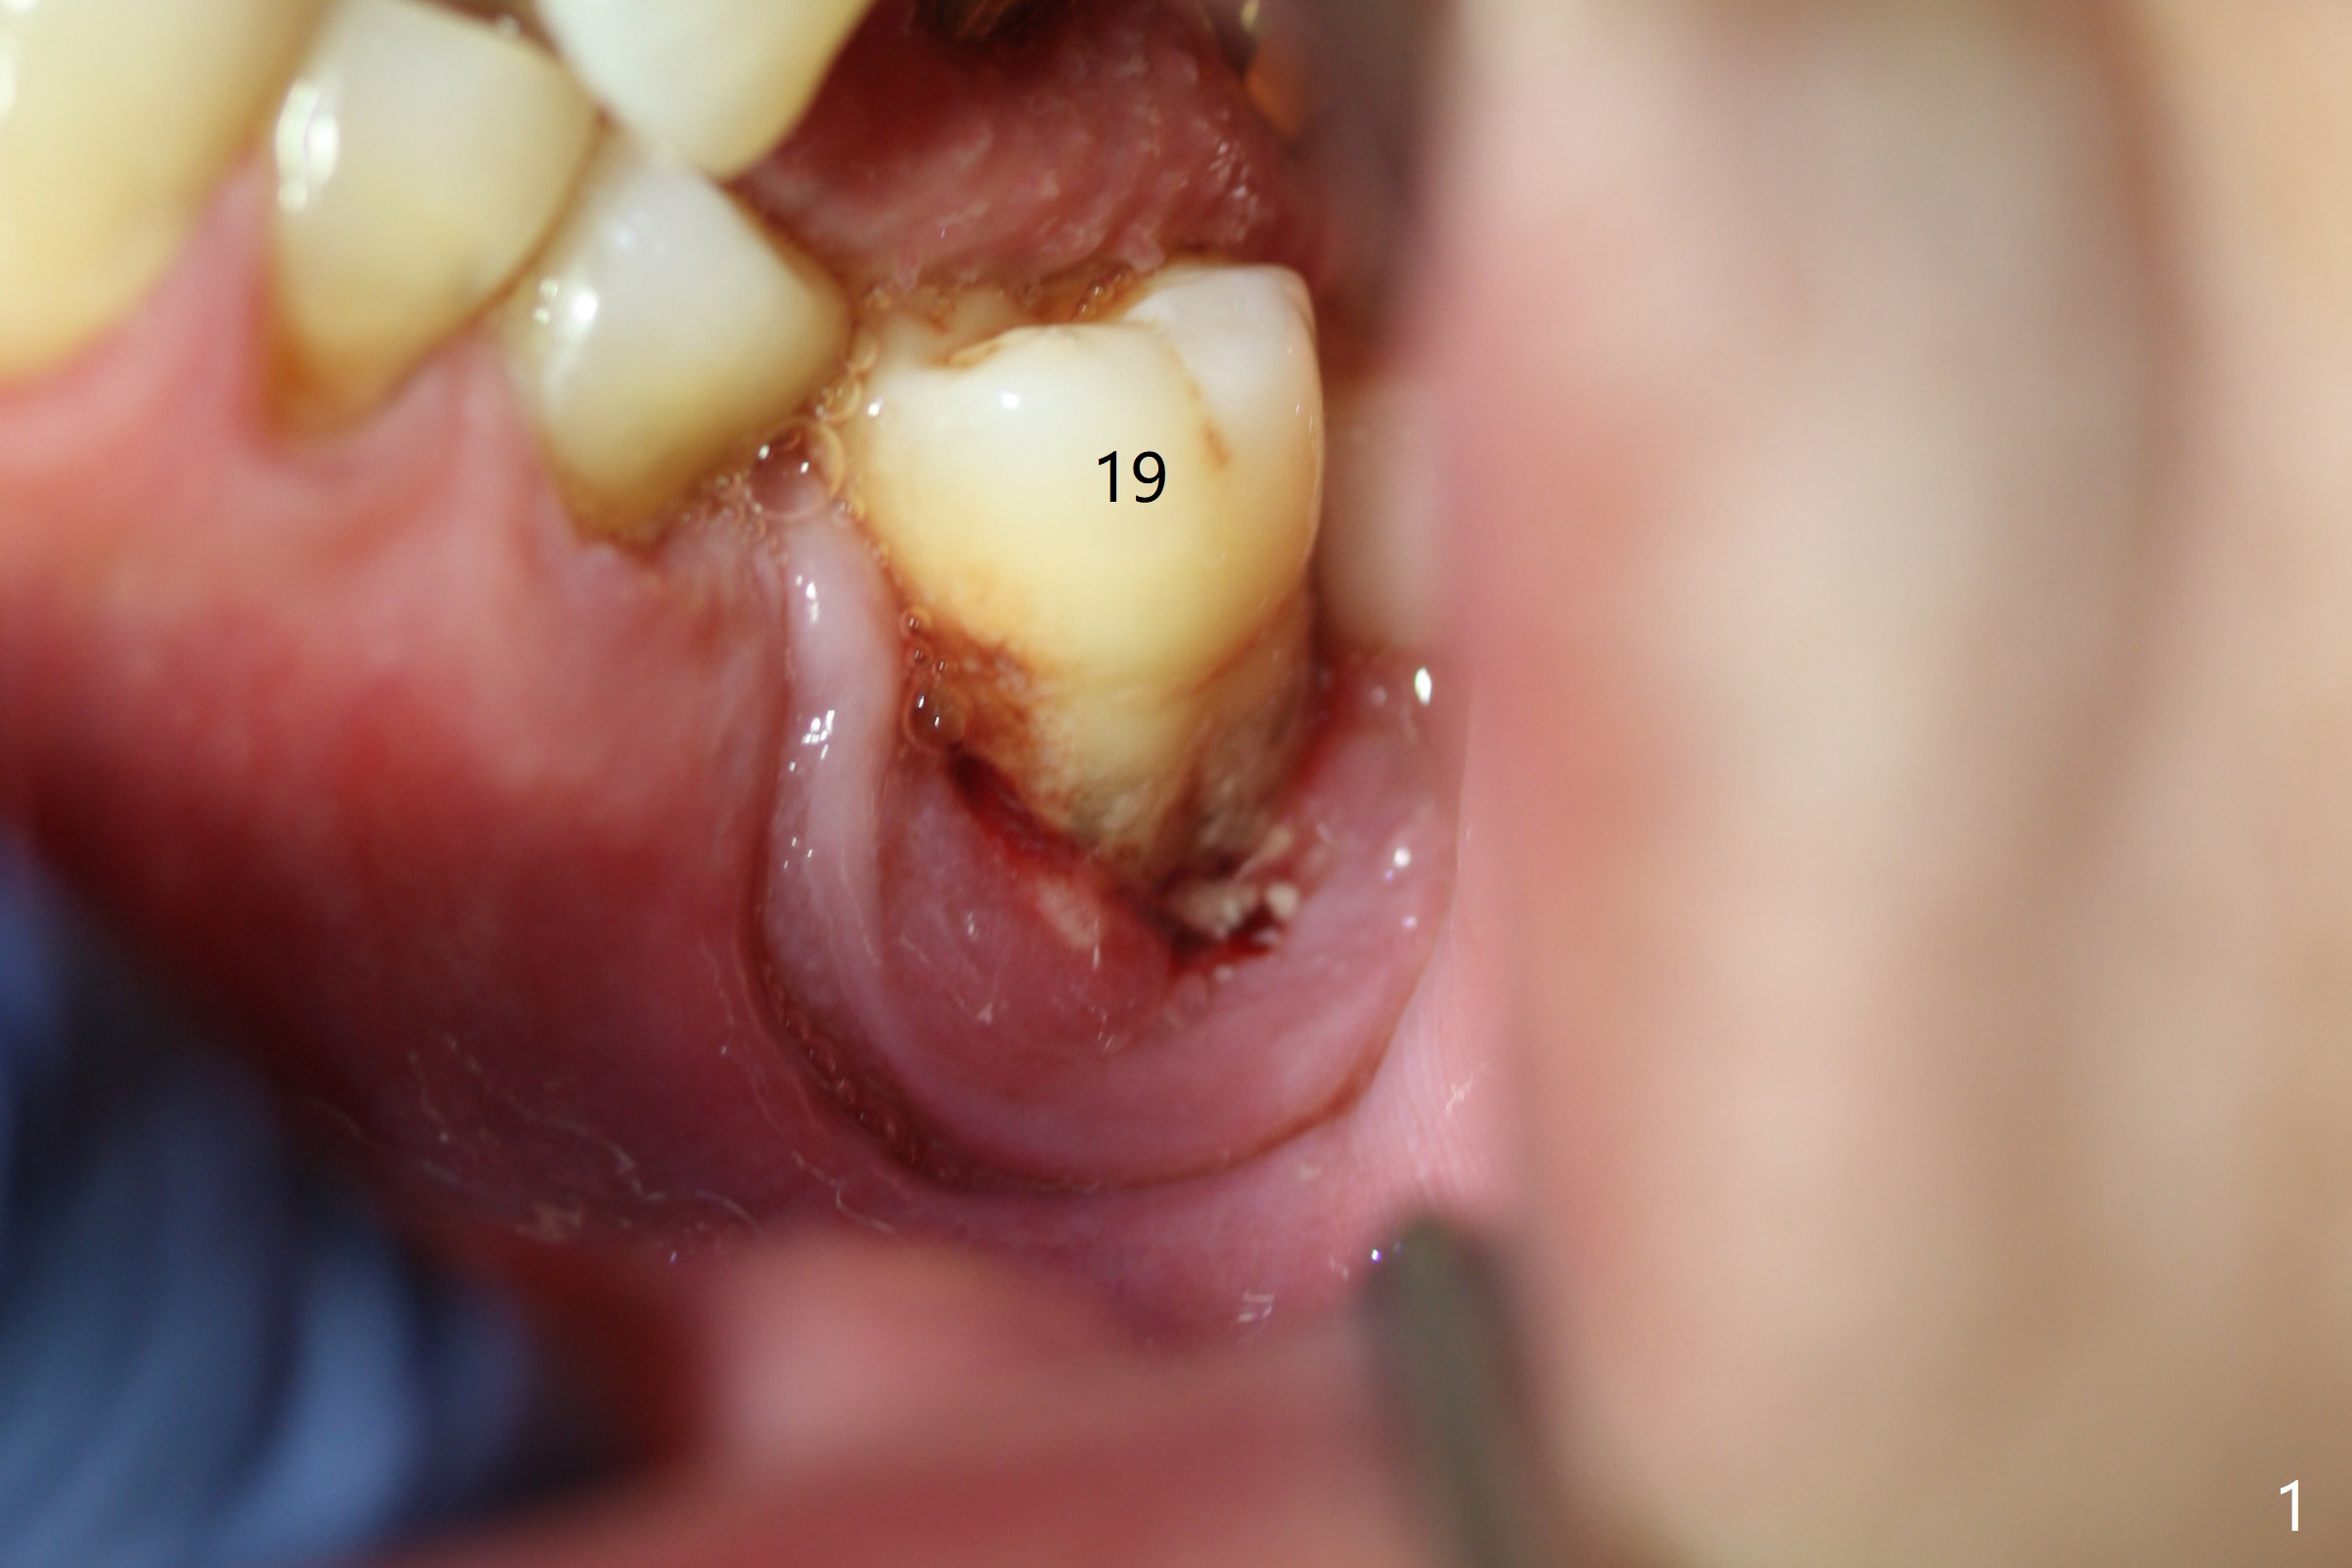

A 67-year-old man requests treatment for the tooth #19 with severe buccal gingival recession (Fig.1). After extraction, a 5x11.5 mm implant will be placed as lingual as possible (Fig.2 L) with ~7 mm buccal implant thread exposure. To reduce the exposure, the implant will be placed deeper, as shown by arrow in Fig.3. PRF membrane and collagen membrane (Fig.4 red line) will be placed against the buccal gingiva, while PRF associated sticky bone (allograft, pink circle) will be packed around the exposed implant threads and a long-cuff abutment (yellow). Finally an immediate provisional (Fig.5 white) will be fabricated to cover the bone graft.